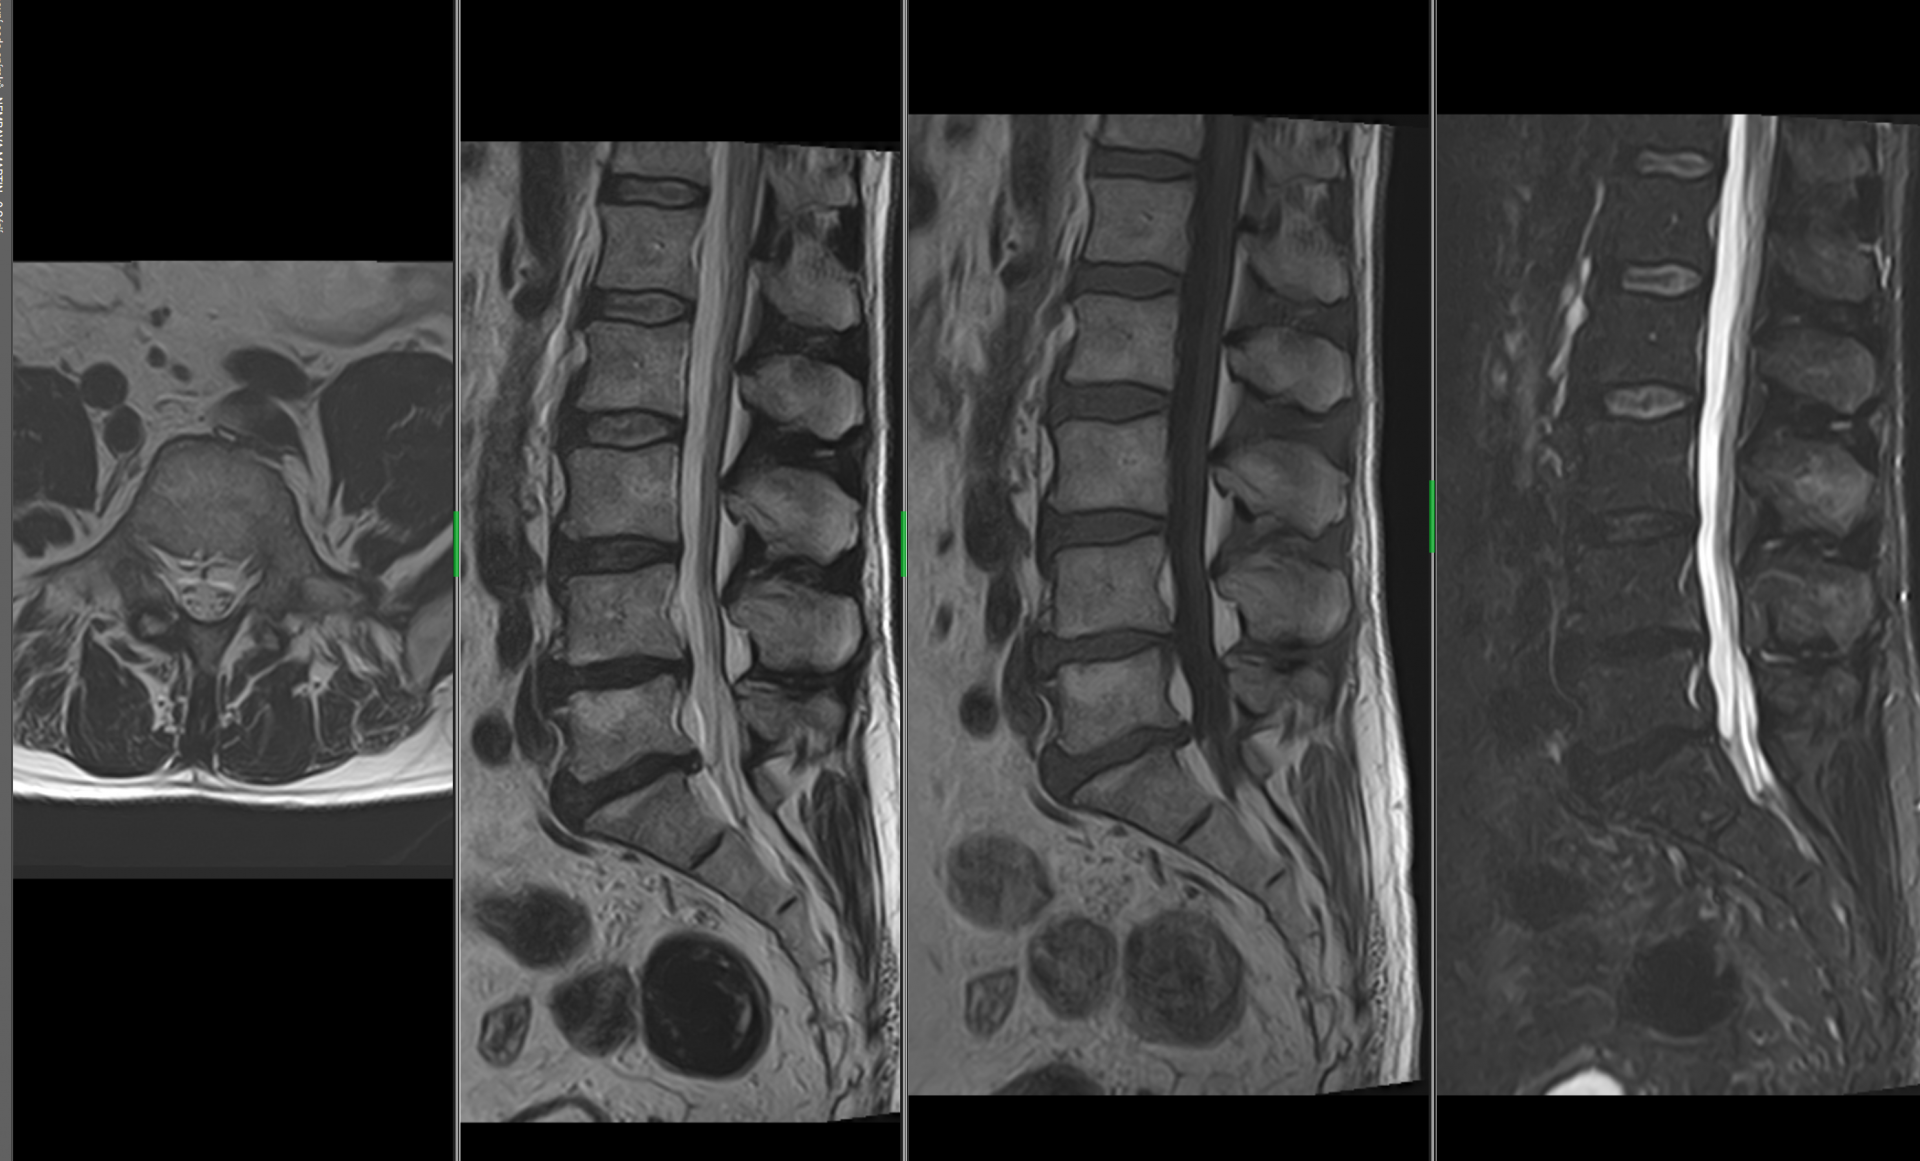

MR páteře

Degenerativní onemocnění (ploténky, vazy, mícha, míšní nervy), metoda volby u nádorových a zánětlivých onemocnění míchy, spinální traumata – akutní vyšetření.

Na našem pracovišti provádíme vyšetření mozku, orbit, hypofýzy, krční páteře, hrudní páteře, bederní páteře, kolenního kloubu, ramenního kloubu, jater a pankreatu, MRCP, ledvin a nadledvin, pánve, MR enterografii, MR angiografii intrakraniálních tepen, MR angiografii mozku – venózní, MR angiografii karotid, MR angiografii tepen dolních končetin, MR angiografii renálních tepen a vyšetření ostatních kloubů těla.